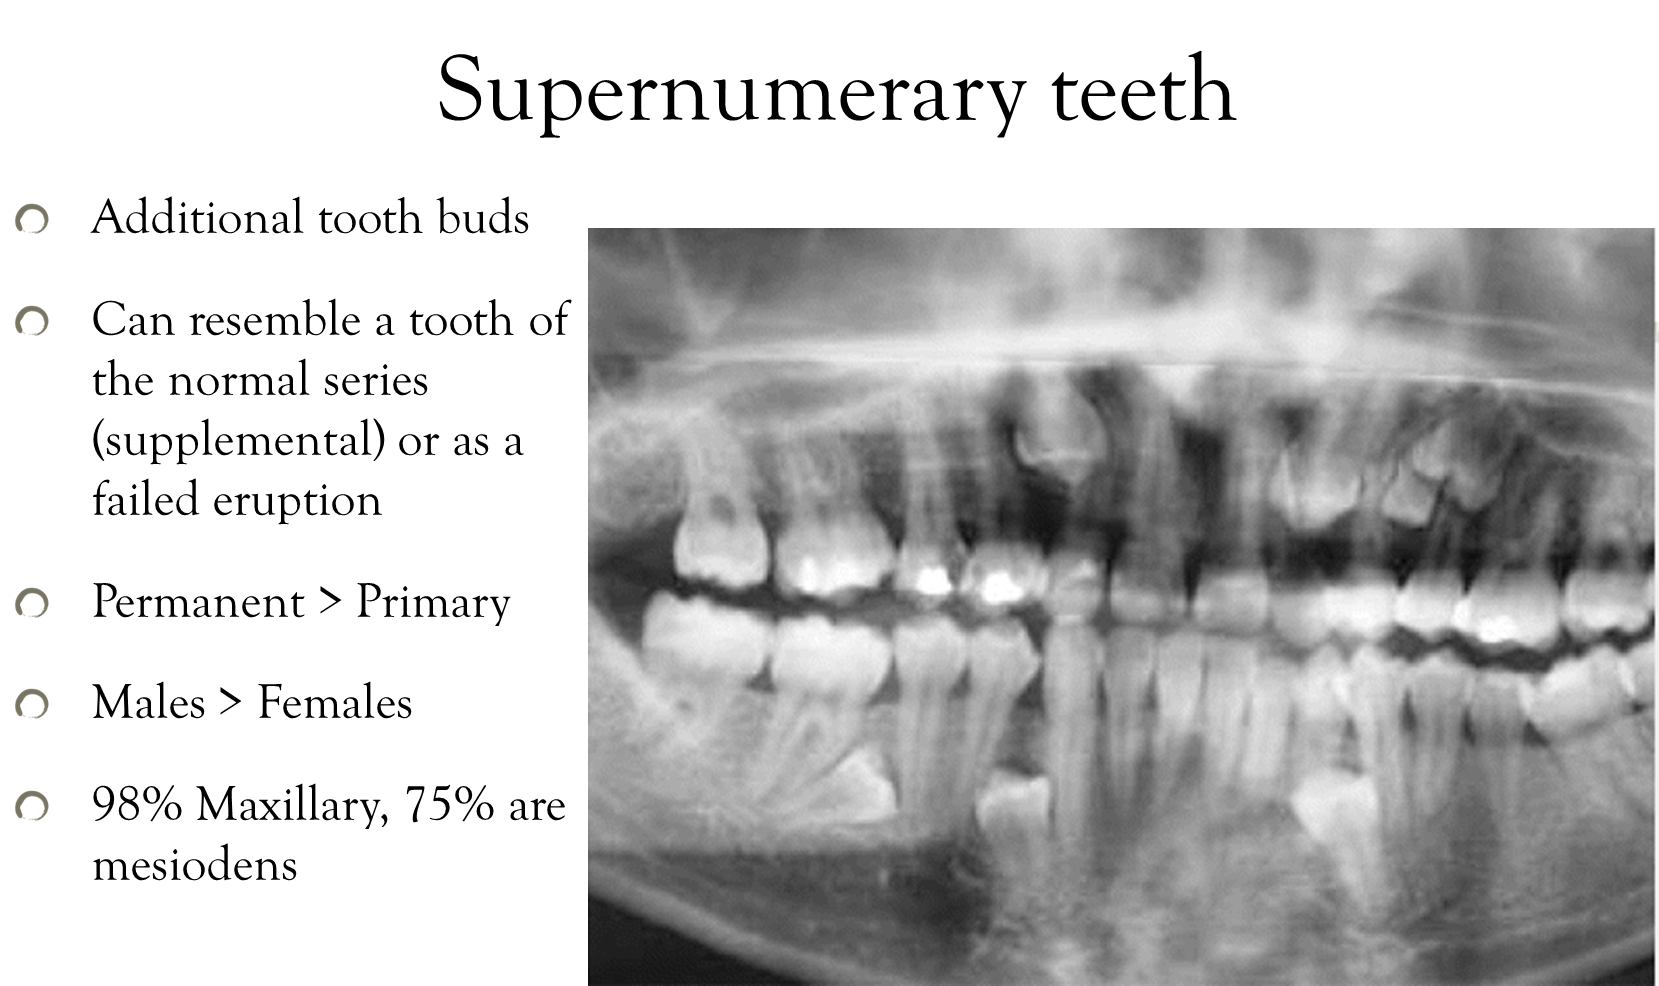

Referred to as extra teeth

More so with permanent than primary, more males than females.

Mesio= midline, Dens= tooth (i.e. central incisor)

Gardner’s Syndrome is another condition characterized by the occurrence of multiple, impacted supernumerary teeth

Also known as familial colorectal polyposis, an autosomal dominant form of polyposis

This disease is of interest to the dental profession because the presence of supernumerary teeth and multiple osteomas in the mandible and maxilla may lead to its diagnosis